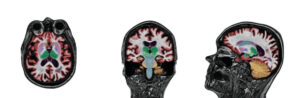

NeuroQuant® is an FDA-cleared software that provides precise volumetric measurements of brain structures by analyzing standard brain MRI images. It helps physicians detect and track subtle brain changes associated with neurological conditions that may not be visible through visual inspection alone.

• Measures volumes of specific brain structures such as the hippocampus, ventricles, and cortical regions

What NeuroQuant® measures:

• Hippocampus (critical for memory)

• Ventricles (fluid-filled spaces)

• Cortical gray matter

• White matter

• Specific brain lobes (frontal, temporal, parietal, occipital)

NeuroQuant® provides age-, sex-, and intracranial volume-adjusted percentiles to identify deviations from normal ranges.